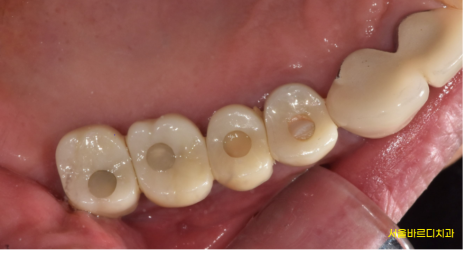

시간이 흘러 뽄을 뜨는 날 사진입니다.

예전에는 1개 어금니가 없었지만

예전에 씌운 이 임플란트로 교체하면서

치아 개수에 맞춰 치료를 해드렸습니다.

그 결과..?

240122

치아 개수가 부족해

씹는 힘이 약했던 부위를

임플란트로 교체 완료하였습니다.